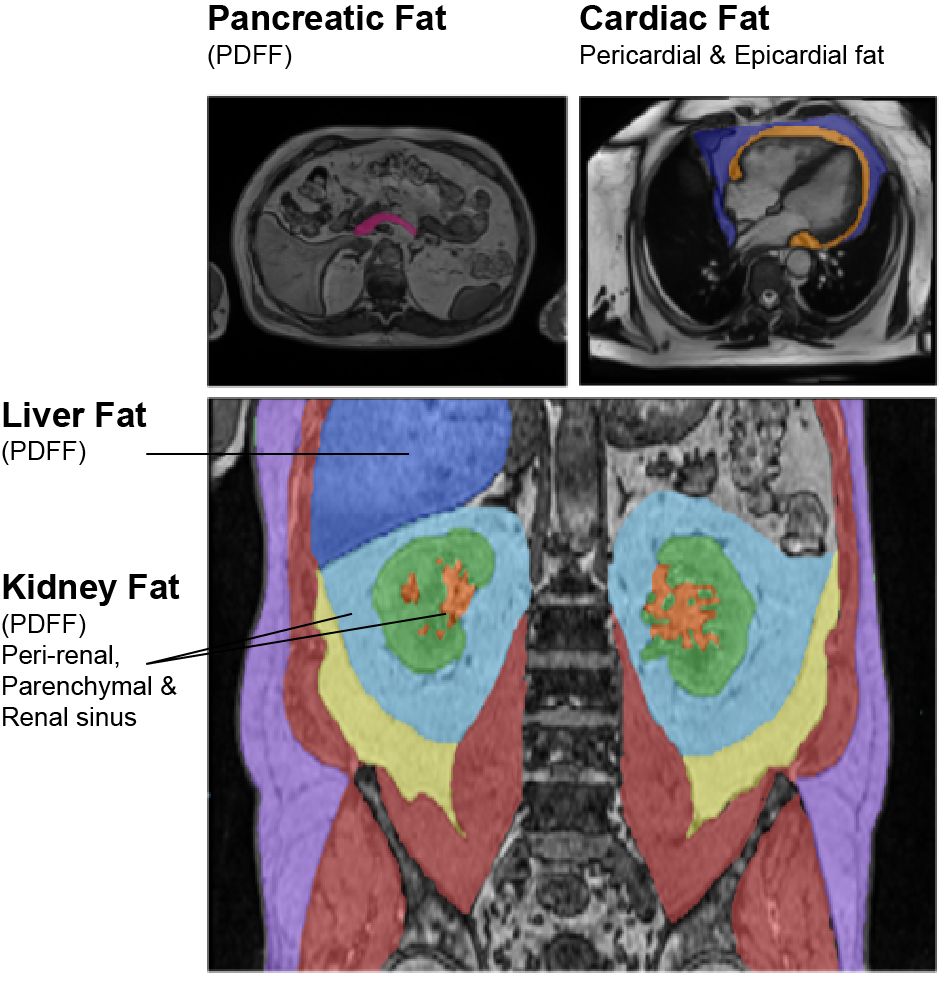

Ectopic fat – impairs organ health and is one of major factors in cardiometabolic disease development

Multi-organ ectopic fat